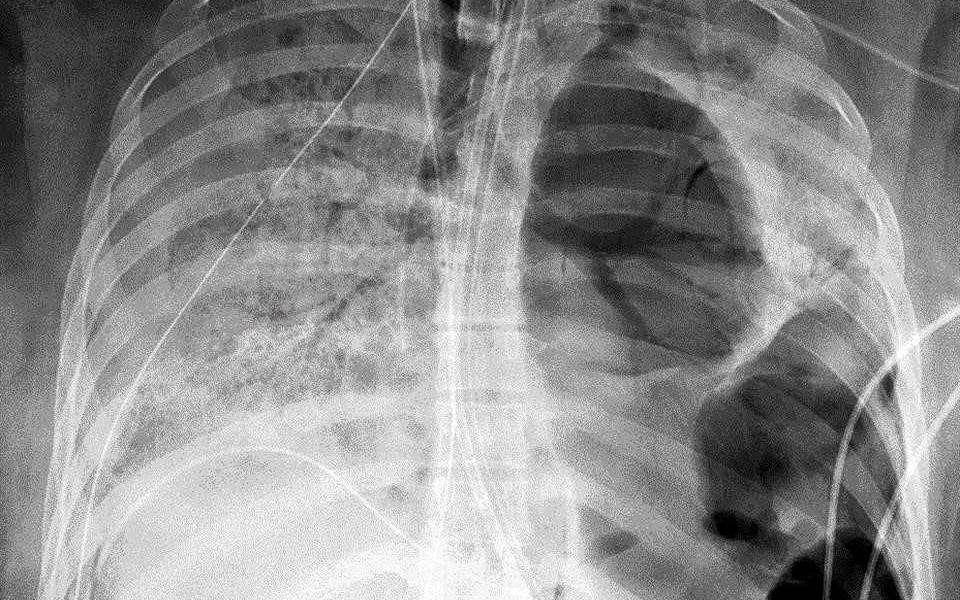

En los primeros días de la pandemia en la ciudad de Nueva York (Estados Unidos), los médicos tenían serios debates sobre si los pacientes con COVID-19 desarrollaban el Síndrome de Dificultad Respiratoria aguda (SDRA) típico o si sufrían un fenómeno completamente diferente.

La principal discrepancia fue que los pacientes con hipoxemia grave a menudo tenían una distensibilidad pulmonar bien conservada; sus pulmones no estaban "rígidos", como se ve en el SDRA típico.

Ahora, un equipo del Hospital Mount Sinai cree que pueden tener una explicación para esa desconexión, y fue un hallazgo completamente fortuito, según Alexandra Reynolds y Hooman Poor, quienes publicaron sus hallazgos en una carta en el American Revista de medicina respiratoria y de cuidados intensivos.